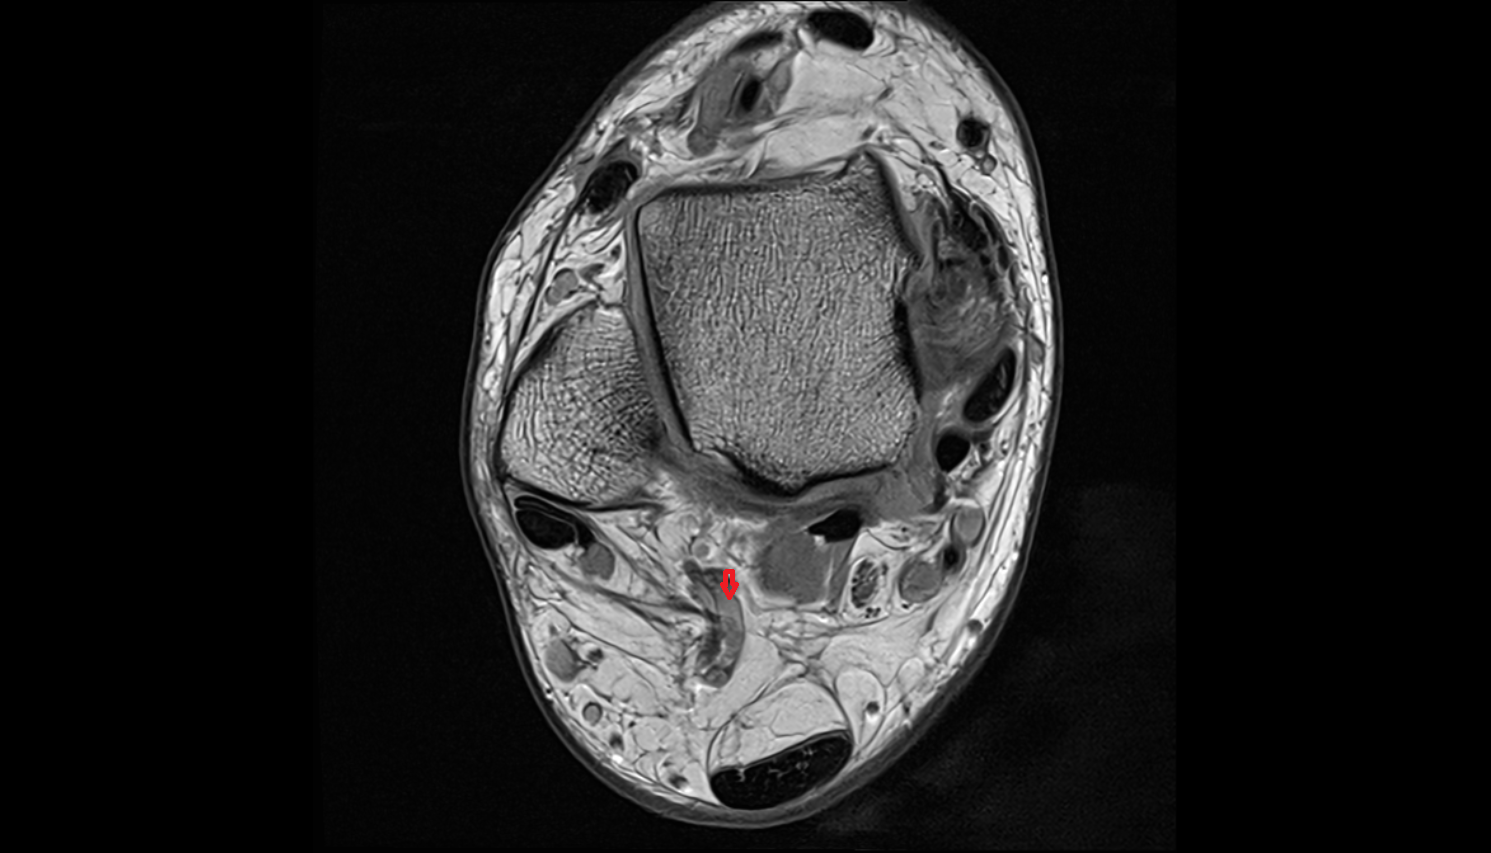

- Calcaneus

- Sustentaculum tali

- Medial malleolus

- Lateral malleolus

- Ankle joint

- Tibialis posterior tendon

- Achilles tendon